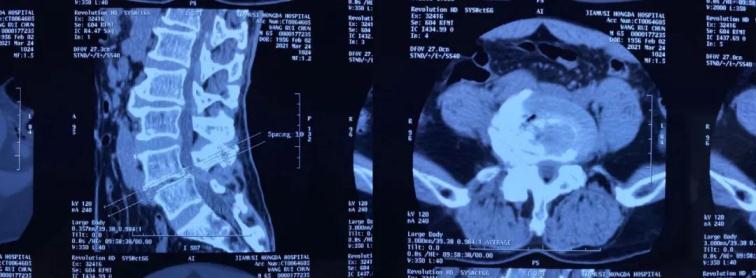

患者王某,男,65歲,腰痛伴右下肢麻痛1年,坐起及行走時(shí)疼痛明顯加重,行走不足100米即疼痛難忍需要休息,保守治療無(wú)效,嚴(yán)重影響生活質(zhì)量。慕名來(lái)到我院并找到喬院長(zhǎng)尋求治療?;颊呷朐汉?,經(jīng)過喬院長(zhǎng)認(rèn)真細(xì)致的檢查,診斷為:腰椎管狹窄、腰椎滑脫。

術(shù)前CT

術(shù)前MRI